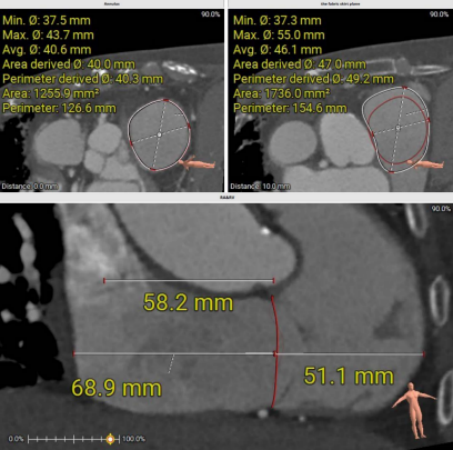

术前评估是本例成功实施的重要基础。患者接受多层螺旋CT(MSCT)检查,对三尖瓣环进行三维重建与精确测量,以评估解剖适配性,并选择合适型号(30–45 mm)的人工瓣膜。